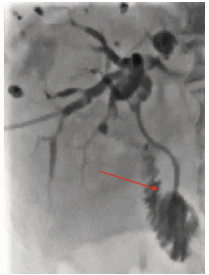

Multidisciplinary treatment of hepatocellular carcinoma with tumor thrombosis in the left portal vein: A case report

Jihong YANG, Guoxiang CHEN, Mo ZHOU, Jisen ZHAO, Yuan WANG, Yuanlong ZHOU

2021, 37(3): 666-679. DOI: 10.3969/j.issn.1001-5256.2021.03.031

Abstract(1185) HTML (567) PDF (3239KB)(69)

Abstract: